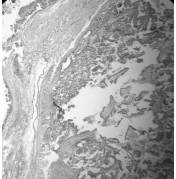

IV.Экстракапсулярная инвазия. При инвазивном росте рака возможно очаговое или обширное распространение за пределы капсулы щитовидной железы в окружающие мягкие ткани (экстрати- реоидная инвазия). Экстратиреоидная инвазия отмечалась в 5% случаев папиллярного (рис. 5) и 3% фолликулярного рака (рис. 6). С ней чаще были связаны регионарные рецидивы и отдаленные метастазы, которые в свою очередь становились причиной смерти.

Рис. 5. Экстратиреоидная инвазия при папиллярном раке щитовидной железы.

Окраска гематоксилином и эозином. X 100

Рис. 6. Широкий инвазивный рост в капсулу и экстратиреоидная инвазия при

фолликулярном раке щитовидной железы.Окраска гематоксилином и эозином. X 100.